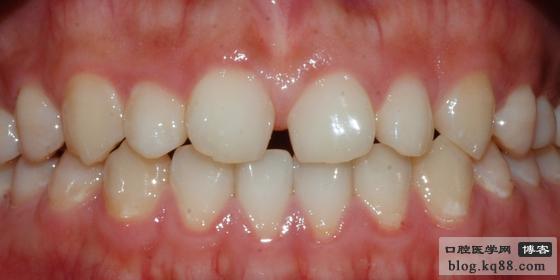

患者女 24歲,要求修復(fù)門牙間隙、取模分析后發(fā)現(xiàn)患者前牙長(zhǎng)寬比例不協(xié)調(diào),牙齒形態(tài)不美觀,為了達(dá)到微創(chuàng)修復(fù),建議患者正畸后再行修復(fù)

口內(nèi)照